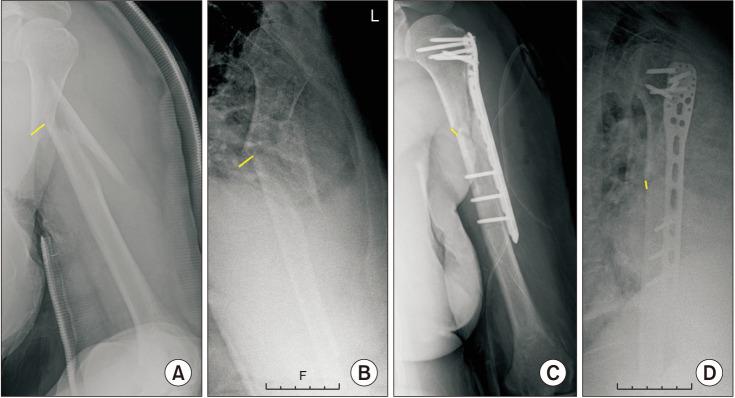

This study compares the difference in the clinical and radiologic outcomes when minimally invasive plate osteosynthesis (MIPO) technique is performed with or without using a positional screw in the treatment of humeral shaft fractures.

本研究比较了在肱骨干骨折治疗中采用微创钢板接骨术(MIPO)时使用或不使用定位螺钉的临床和影像学结果差异。

2010年1月至2021年1月,对共63例行MIPO技术治疗肱骨干骨折的患者进行回顾性研究。我们将这些患者分为两组:第一组患者行不使用定位螺钉的MIPO;第二组患者行使用定位螺钉的MIPO。我们比较了功能结果,包括美国肩肘外科医师评分、加州大学洛杉矶分校评分、简易肩关节测试、手术前后的活动范围、手术时间、失血量和并发症。并且我们比较了影像学结果,包括术前和术后骨折的前后位(AP)和侧方移位以及X线平片上的愈合时间。

患者平均年龄为64.6±15.1岁(范围25 - 88岁)。第一组由30例患者组成(10例男性和20例女性),第二组由33例患者组成(11例男性和22例女性)。两组之间在性别、体重指数、功能评分、术后X线片上骨折的AP和侧方移位、手术时间和失血量方面无统计学显著差异。在第二组中,获得骨愈合的速度比第一组更快(4.6个月对6.4个月)。并发症包括两组各2例短暂性桡神经麻痹和金属植入物失败(第一组2例,第二组1例)。

在对肱骨干骨折进行MIPO时,添加定位螺钉可能比不使用定位螺钉的桥接钢板更具稳定性,从而导致更快的骨愈合。定位螺钉可能有助于控制骨折块间运动,而不抑制骨折愈合所需的必要骨折块间运动。